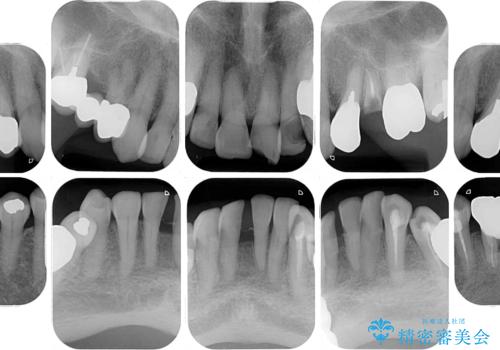

- 長年気にしていた捻れた前歯が欠けたとのことで来院された患者様です。

矯正治療に抵抗があったそうですが、前歯が欠けたことをきっかけに、矯正治療で歯列を整えた上で、セラミッククラウン治療を行う決心が付いたとのことでした。

デコボコが強いため、ブリッジや残根となっている部分のスペースを利用して歯列を整え、変色や欠けている歯をオールセラミッククラウンによる補綴治療を行うこととしました。